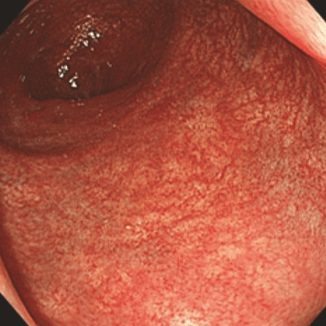

Умеренная активность воспалительного процесса:

yazvennyi_kolit.png

ЯК умер акт-min.png

Умеренная активность

Гиперемия и отек

диффузные

Зернистость

есть

Сосудистый рисунок

отсутствует

Кровоточивость

субэпителиальные геморрагии + умеренно выраженная контактная ранимость

Эрозии

множественные

Язвы

единичные